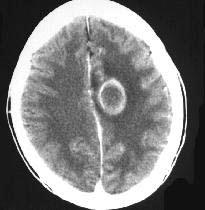

成年男性,头疼、头胀、发热,血象高,CT检查如图,选择最可能的诊断()A.脑脓肿B.胶质瘤C.皮样囊肿D.脑梗死E.脑膜瘤

问题 成年男性,头疼、头胀、发热,血象高,CT检查如图,选择最可能的诊断()

选项 A.脑脓肿 B.胶质瘤 C.皮样囊肿 D.脑梗死 E.脑膜瘤

答案 A